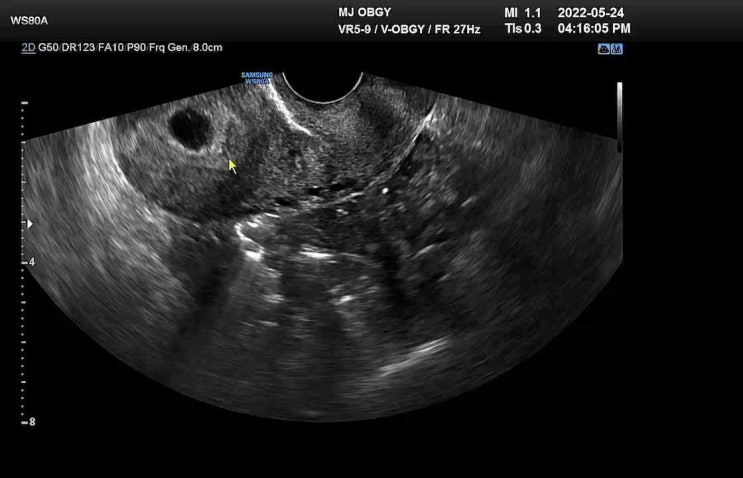

文章的部落格點進去還會有超音波影片;;;

https://m.blog.naver.com/cinnamoroll211/223205311149